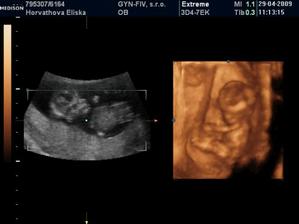

Dvojicky po KET

tak sme sa dockali-nase dvojicky sa narodili v 37+1 tt -20.10.09 cisarskym rezom -11:00 Matúško 3150g a 48cm a 11:02 Natálka 3030g 48cm,